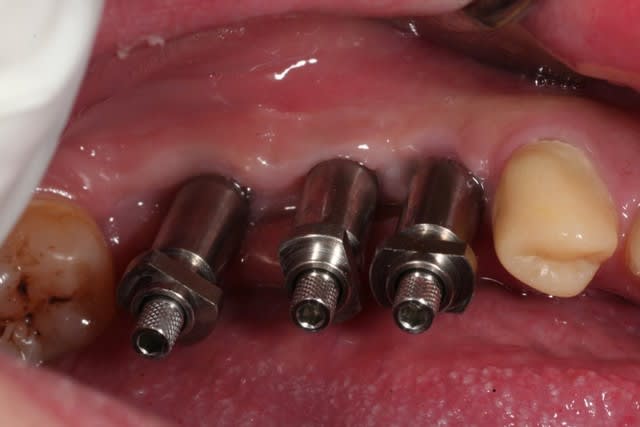

on continue avec ce cas...

ces quelques images ont pour but de dédramatiser la prothèse sur implants, et bien montrer que ce n'est pas pire qu'Ikéa...

alhoun

pour ceux qui ne sont pas familiers avec ce type de procédure, les questions sont les bienvenues.

est ce que tu solidarises tes transferts entre eux avant l'empreinte ?

tu ne protèges pas tes vis pour devisser plus facilement en pick up avec cire ou autre perso je mets de la cire d'ortho(celle pour éviter les blessures) qu'on enlève très facilement ?http://www.eugenol.com/eugenol/file.php?21,file=14295

quel matériau d'empreinte(DMG) ?

.

non, je ne solidarise pas sur une petite portée comme ça. quand c'est plus grand, je passe à l'empreinte au plâtre.

ici c'est du pentasoft, et si tu regardes bien, les têtes de vis sont accessibles pour le dévissage.